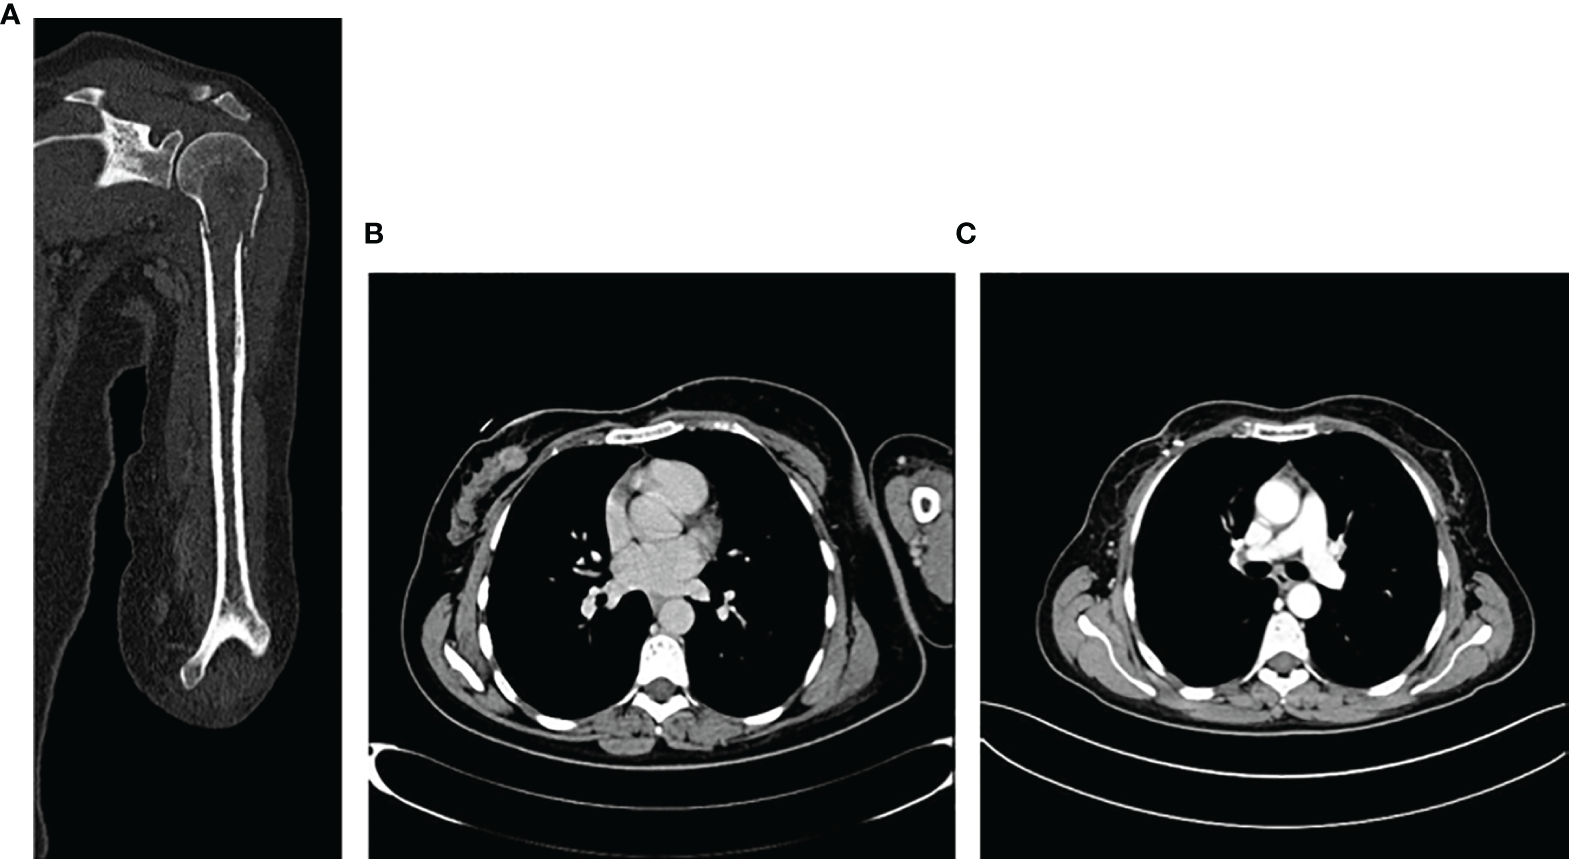

According to the advanced disease stage, in August 2019 she started first-line treatment with ribociclib plus letrozole with the adjunct of a bisphosphonate to prevent skeletal events. However, due to bone pain being non-responsive to painful drugs, in September 2019, the patient also underwent a palliative stereotactic radiotherapy of the left iliac wing and the 10th rib (3,000 cGy on each site), with immediate pain improvement. Overall, the treatment was well tolerated, and only G1 nausea, unspecific osteomuscular pain, and G1 hypercholesterolemia were reported. In December 2019, at the first clinico-radiological evaluation partial response of both breast and axilla localizations, even with the persistency of a satellite nodule, as well as a significant reduction in bone lesions at the bone scan, was reported (Figure 5).

Figure 5

Bone scan evaluation, before and after treatment with ribociclib and letrozole.

In May 2020, an 18FDG-PET CT showed a mild pathological expression of glucidic metabolism in correspondence to bone rearrangement areas with mixed characteristics to the level of the right iliac wing (SUV 2.1) and to the level of the 10th left rib (SUV 2.5). After 4 months, a further reduction in the dimension of breast cancer as well as ipsilateral lymphadenopathies, with no more evidence of satellite nodules, was reported at both mammary ultrasound and breast resonance imaging. Moreover, the 18FDG-PET CT was negative for secondary lesions. Subsequently, in December 2020 the local breast unit choice was surgery of primary tumor and maintenance of systemic endocrine treatment which is still ongoing with good tolerability.